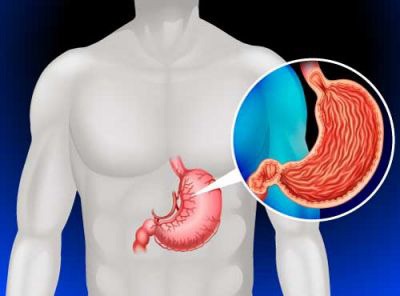

بیشتر بخوانید »نشانههای هشدار دهنده سرطان معده بی ارتباط با درد

سرطان معده یکی از دردناکترین انواع سرطان محسوب می شود. درد مرتبط با سرطان معده حالتی پایدار دارد و این گونه نیست که یک روز آن را احساس کنید، دو هفته از بین برود و دوباره باز گردد. درد کلاسیک سرطان معده دردی مبهم در میانه معده است. اما برای بسیاری از مبتلایان به سرطان معده ممکن است احساس درد …

بیشتر بخوانید »9 عادتی که باعث افزایش خطر سرطان معده می شود

مصرف برخی مواد غذایی، نوشیدنی ها، بهداشت نادرست زندگی و غیره جزو عواملی هستند که معده را به دردسر انداخته و حتی خطر بروز سرطان را افزایش می دهند. در این مطلب شما را با این عوامل بیشتر آشنا می کنیم. اگر چه اکثر سرطان های معده مربوط به هلیکوباکترپیلوری و عوامل ژنتیکی است اما برخی از این نوع سرطان …